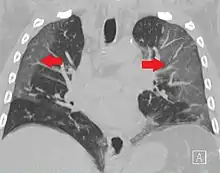

CT image showing ground-glass opacification in the posterior of the right lung (screen left). - Measles